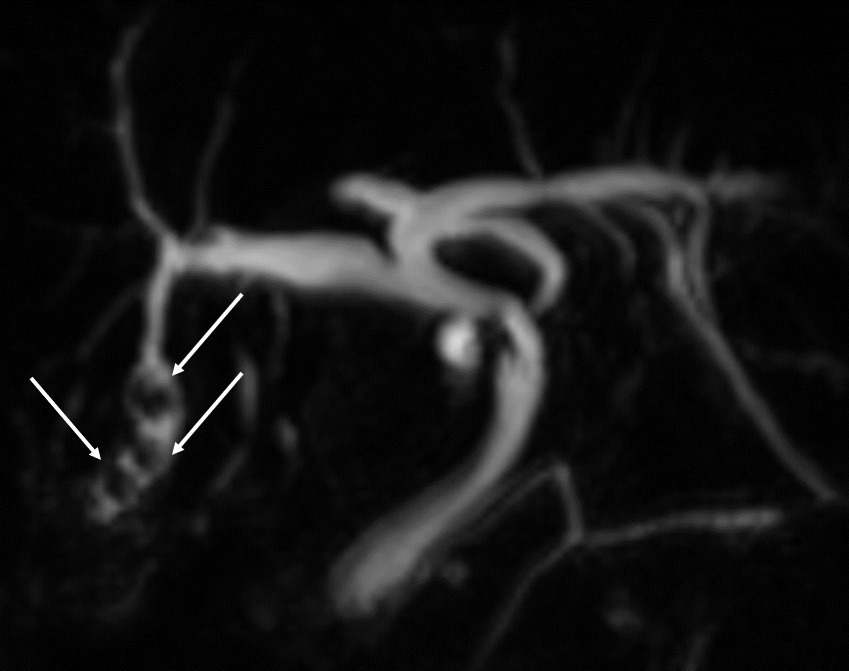

L’échographie hépatique est l’examen clé pour le diagnostic de syndrome LPAC. Celle-ci met typiquement en évidence les signes d’une microlithiase intrahépatique sous la forme d’images en « queue de comète » (échos de répétition liés à la vibration des microcristaux sous le faisceau d’ultrasons), de micro-­spots ou de « boue biliaire » (sludge) le long des canaux intrahépatiques (fig. 1A). Ces signes sont parfois difficilement identifiables, notamment en situation non sensibilisée et pour un opérateur non entraîné. Le principal diagnostic différentiel est représenté par les microhamartomes (ou complexes de von Meyenburg) qui peuvent parfois se présenter sous la forme d’artéfacts en queue de comète.9 Une échographie normale standard n’élimine pas le diag­nostic et il peut être nécessaire de répéter l’examen par un radiologue expérimenté et formé à la sémio­logie du syndrome LPAC. Moins fréquemment (5 à 10 % des cas), le syndrome LPAC peut se présenter sous la forme de vrais calculs (macrolithiases) intra- ou extrahépatiques (fig. 1B).4 Une lithiase vésiculaire n’est observée que chez un tiers des patients atteints de syndrome LPAC.

La cholangiographie par IRM est typiquement normale dans les formes habituelles, microlithiasiques, du syndrome LPAC. Elle n’est donc pas nécessaire au diagnostic dans la très grande majorité des situations. Elle doit être réalisée en cas de calculs intrahépatiques ou de dilatation des canaux biliaires en échographie afin d’évaluer le retentissement de ces calculs sur les voies biliaires et le parenchyme hépatique. Les calculs biliaires ne sont pas toujours visibles à l’imagerie par résonance magnétique (IRM), notamment quand leur taille est inférieure à 5 mm. Lorsqu’ils sont visibles, ils sont le plus souvent visualisés en hyposignal T1 et T2 sous forme de lacunes endobiliaires (fig. 2 A et 2B). Dans une série récente portant sur 125 patients suivis dans un centre expert et ayant tous eu une bili-IRM, 49 % présentaient des anomalies des canaux biliaires, parmi lesquelles 93 % de calculs intra­hépatiques et 38 % de dilatation des canaux biliaires.10 Ces anomalies morphologiques étaient plus fréquemment observées chez les porteurs d’un variant pathogène du gène ABCB4.